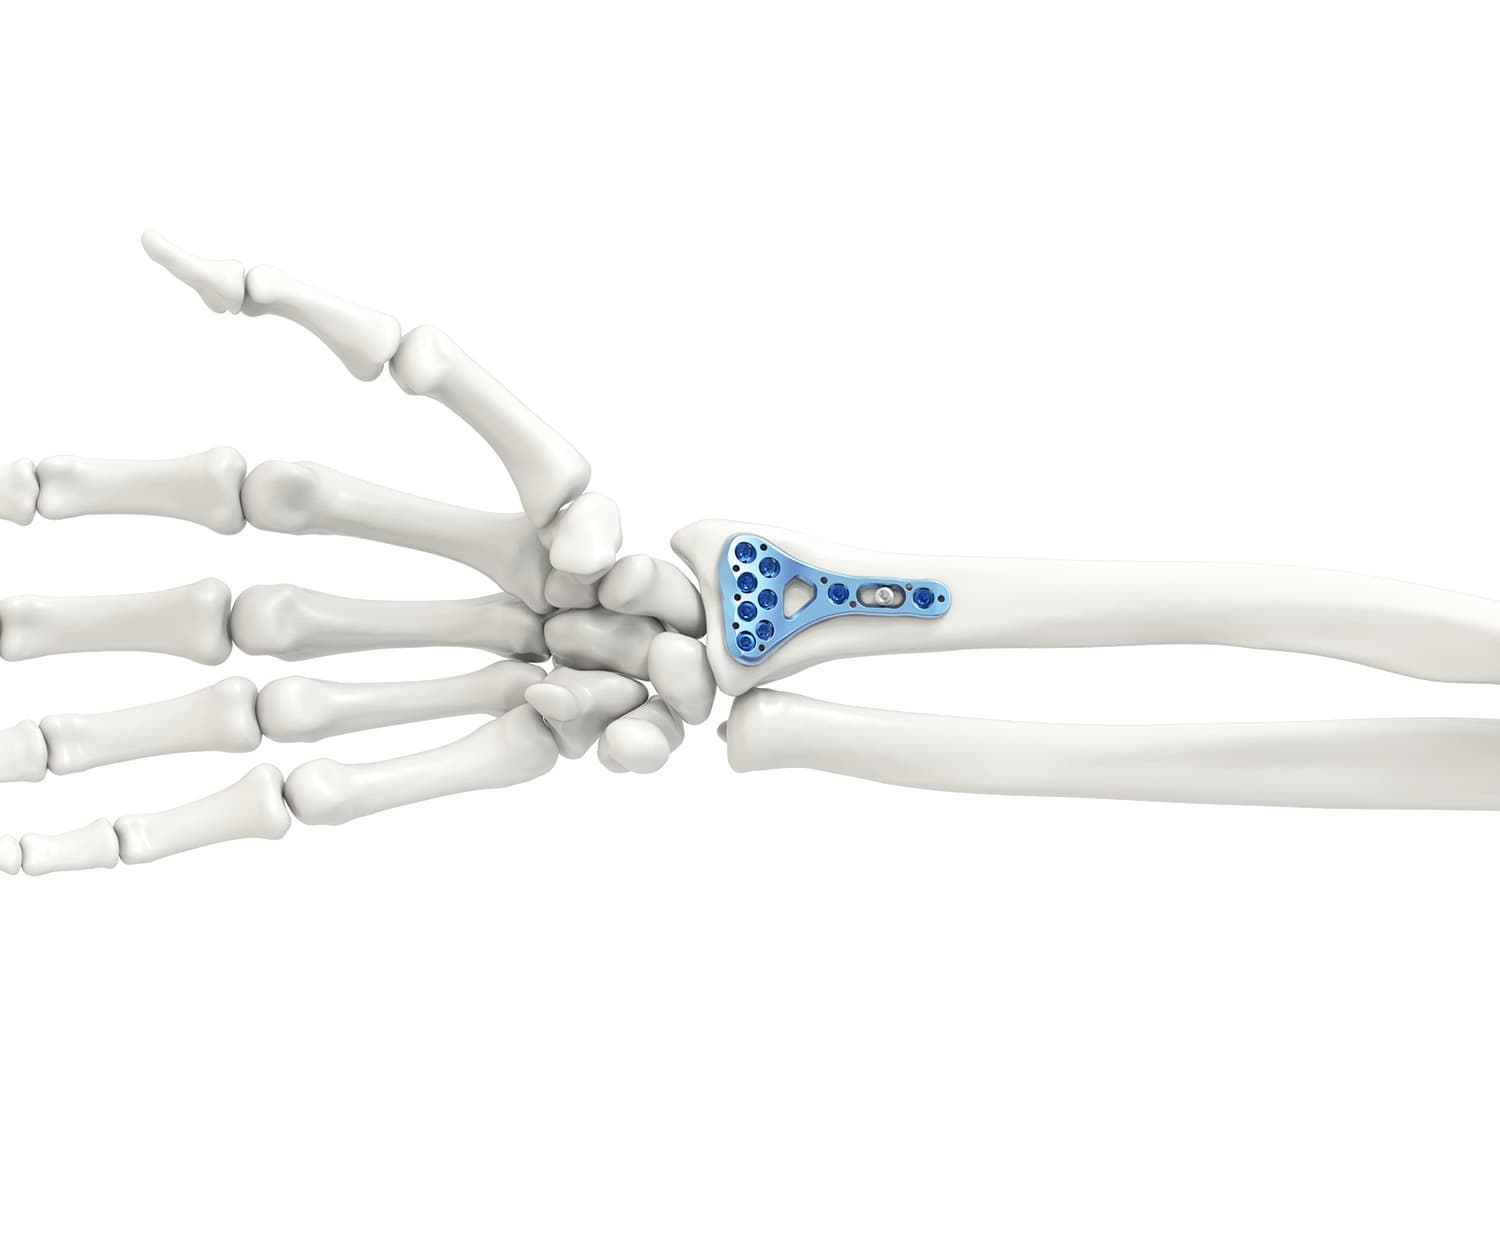

Радиоульнарный угол: строение и особенности лучевой кости